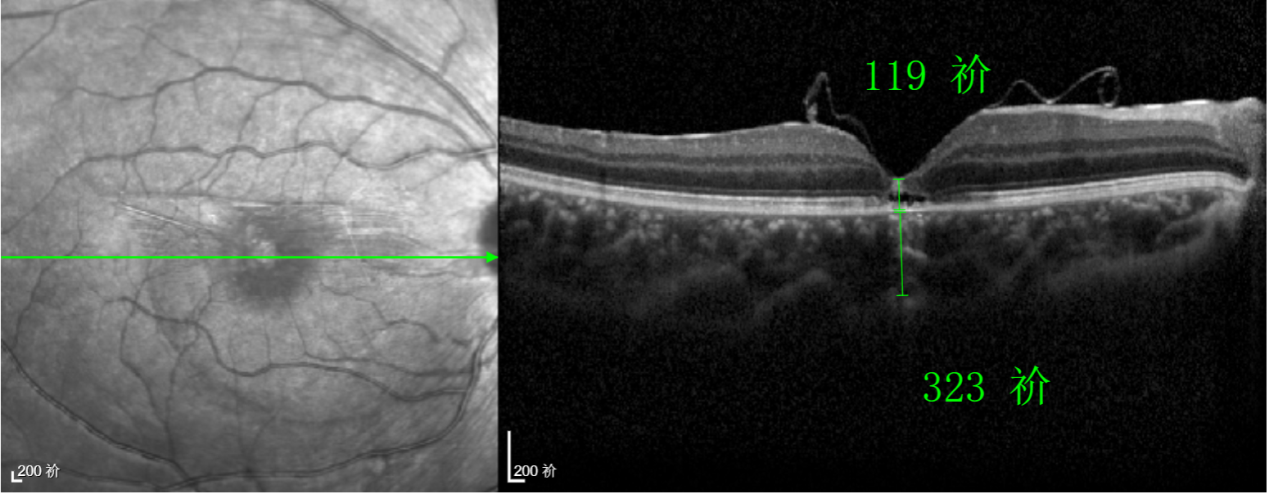

除此之外,利用自體組織覆蓋為黃斑裂孔提供了理想的愈合環(huán)境,裂孔閉合速度顯著快于傳統(tǒng)方法。誠(chéng)誠(chéng)接受手術(shù)24小時(shí)后,檢查可見(jiàn)內(nèi)界膜瓣位置良好;術(shù)后1個(gè)月,黃斑裂孔已經(jīng)閉合,視力恢復(fù)到0.5;術(shù)后兩個(gè)月,視力進(jìn)一步提升到0.7。